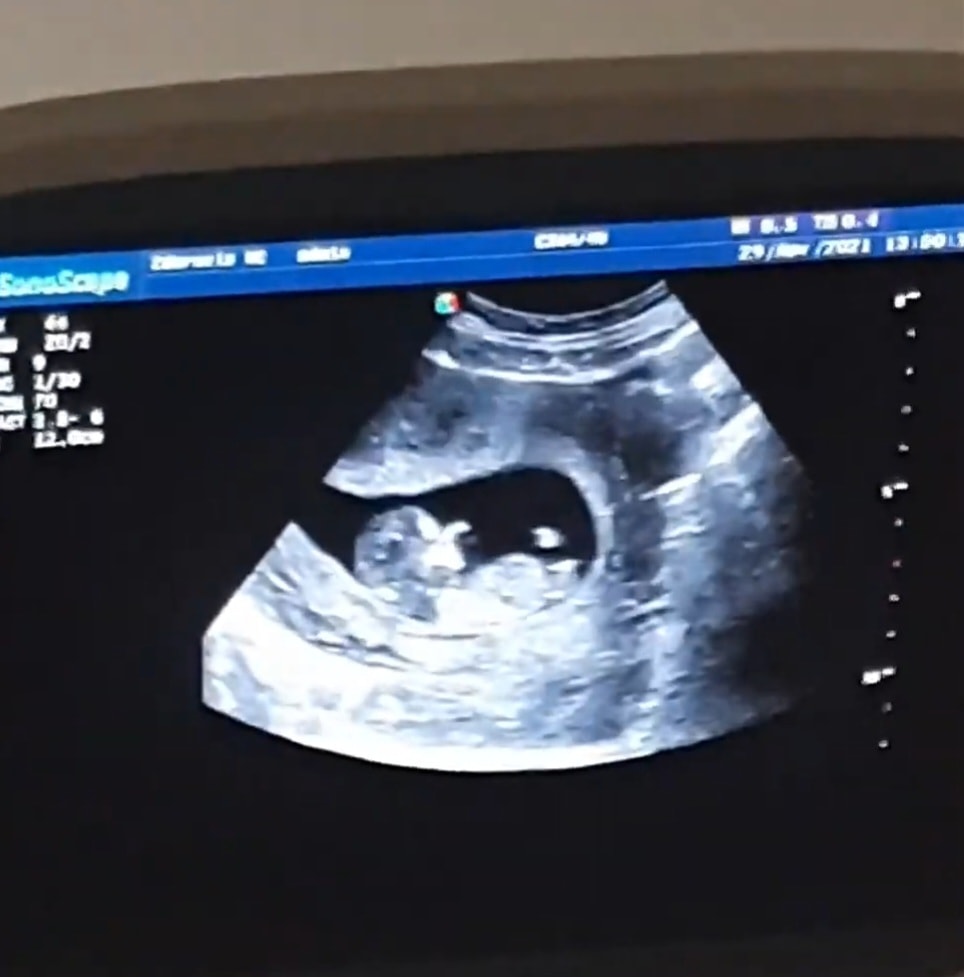

Прикрепляю свои узи, на разных узи разное положение полового бугорка, говорят мальчик, но допустим на второй фотке мне кажется половой бугорок на девочку) что думаете? Читаю разное мнение, что у кого то был прям вверх половой бугорок, а итог девочка и наоборот

сейчас срок по узи 13.2

У меня есть только фото младшего сына с бугорком. Врач тогда предположил мальчика, но смотрел снизу между ног.

А я была уверена, что он ошибся. Но нет, не ошибся)